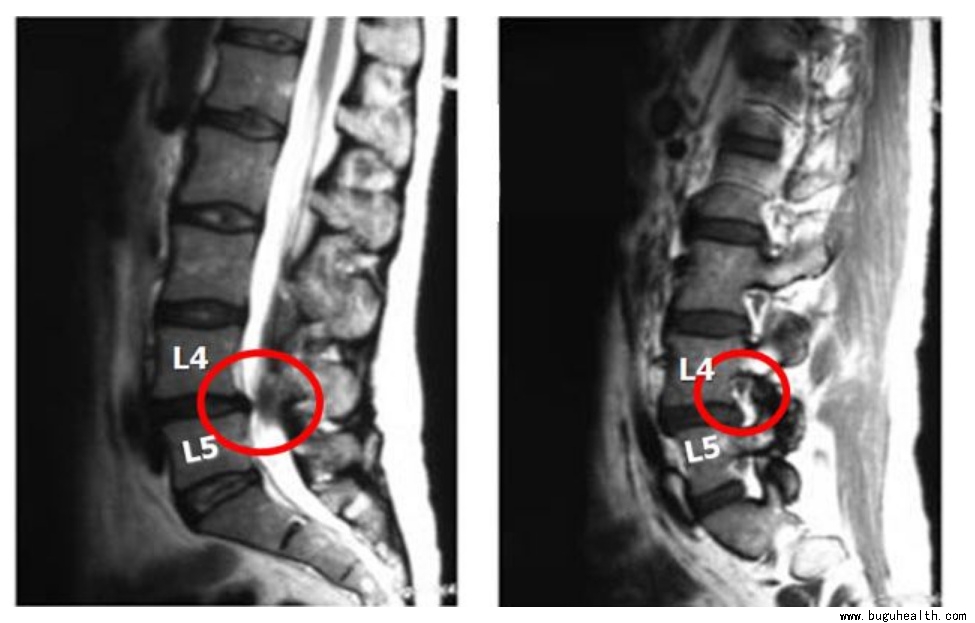

▼ 椎管狭窄典型症状:

1) 大多数腰椎管狭窄症患者,都有下腰痛的病史或伴有下腰痛。疼痛一般比较轻微,卧床休息则减轻或消失,腰前屈不受限制,后伸活动往往受限。

2) 马尾神经压迫症。腰椎管狭窄症可导致马尾神经受压迫,出现马鞍区的症状与体征以及括约肌的症状,严重时可出现大小便及性生活障碍症状。

3) 明显的腰腿痛症状和间歇性跛行

4检查脊椎偏斜不明显,腰椎正常,只是后伸痛。直腿抬高试验正常或只有中度牵拉痛。少数患者下肢肌肉萎缩,跟腱反射有时减弱或消失。

椎管狭窄的诊断要求详细的病史和体格检查,也可通过CTMRI判断,为判断神经功能障碍情况可能需要肌电图检查。